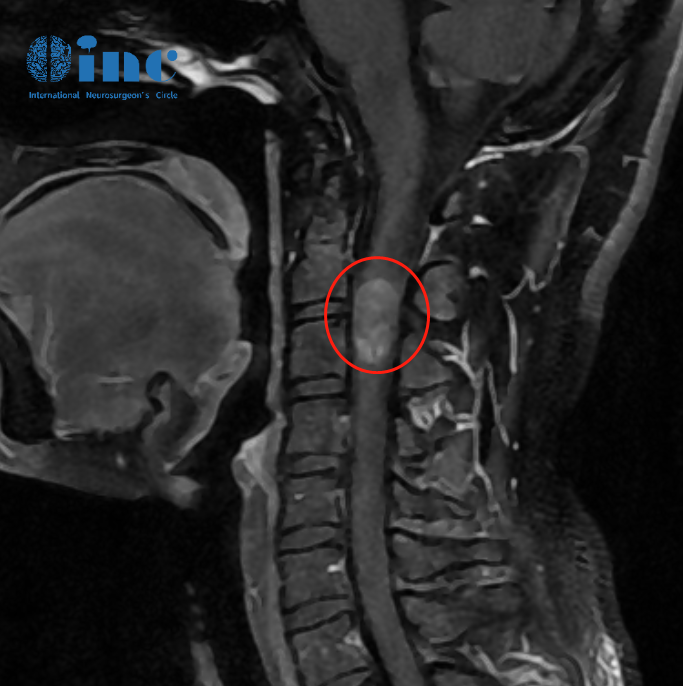

“没有比这更好的了”——28岁的潇潇在脊髓髓内室管膜瘤手术过去整整一年后收到了新年到来前较好的消息,自己的主刀医生巴教授在收到术后1年核磁影像复查资料后表示“肿瘤没有复发,没有任何残留”,潇潇的情况好。

2022年12月4日,巴教授成功为潇潇进行示范教学手术,顺利全切肿瘤。术后这一年中,潇潇正常生活工作,像全部年轻女孩一样潇潇爱美爱玩,摆脱了脊髓髓内“炸弹”后她也更加珍惜现在来之不易的健康。